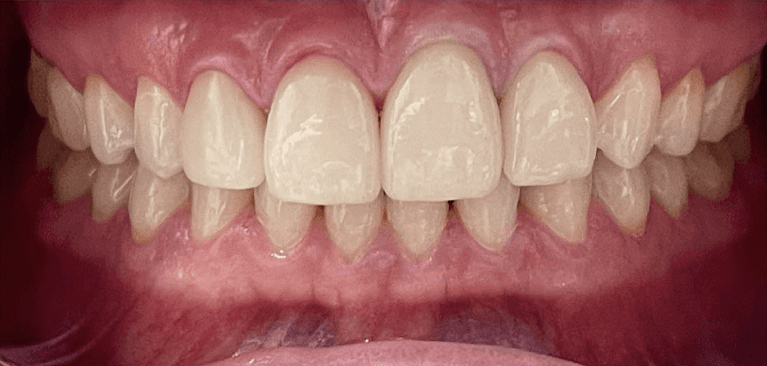

Before and after with Invisalign orthodontic treatment. Pictures taken with different phones at different setting. Used total of 27 aligners/trays. Treatment time 13.5 months